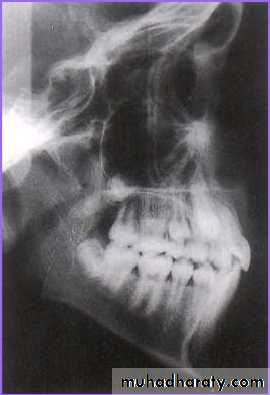

Lateral Cephalogram

Perapical view

First and the most simplest viewAdvantages

1) Root development, pattern and

integrity

2) Crown resorption

3) Root resorption of adjacent tooth

4) Minimum of surrounding tissue is

exposed which increase

accuracy and resolution.

5) Minimal radiation exposure

Disadvantage

1) 2D picture of 3D object

2) cannot determine bucco-lingual

position of tooth & vertical

position of impacted tooth.